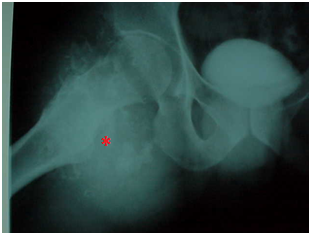

Grande massa no fêmur causada por osteossarcoma.

Osteossarcoma. Presença de osteóide (*) e o grande pleomorfismo celular e nuclear, conforme indicam os núcleos circulados sugerem padrão de diferenciação compatível com essa neoplasia.